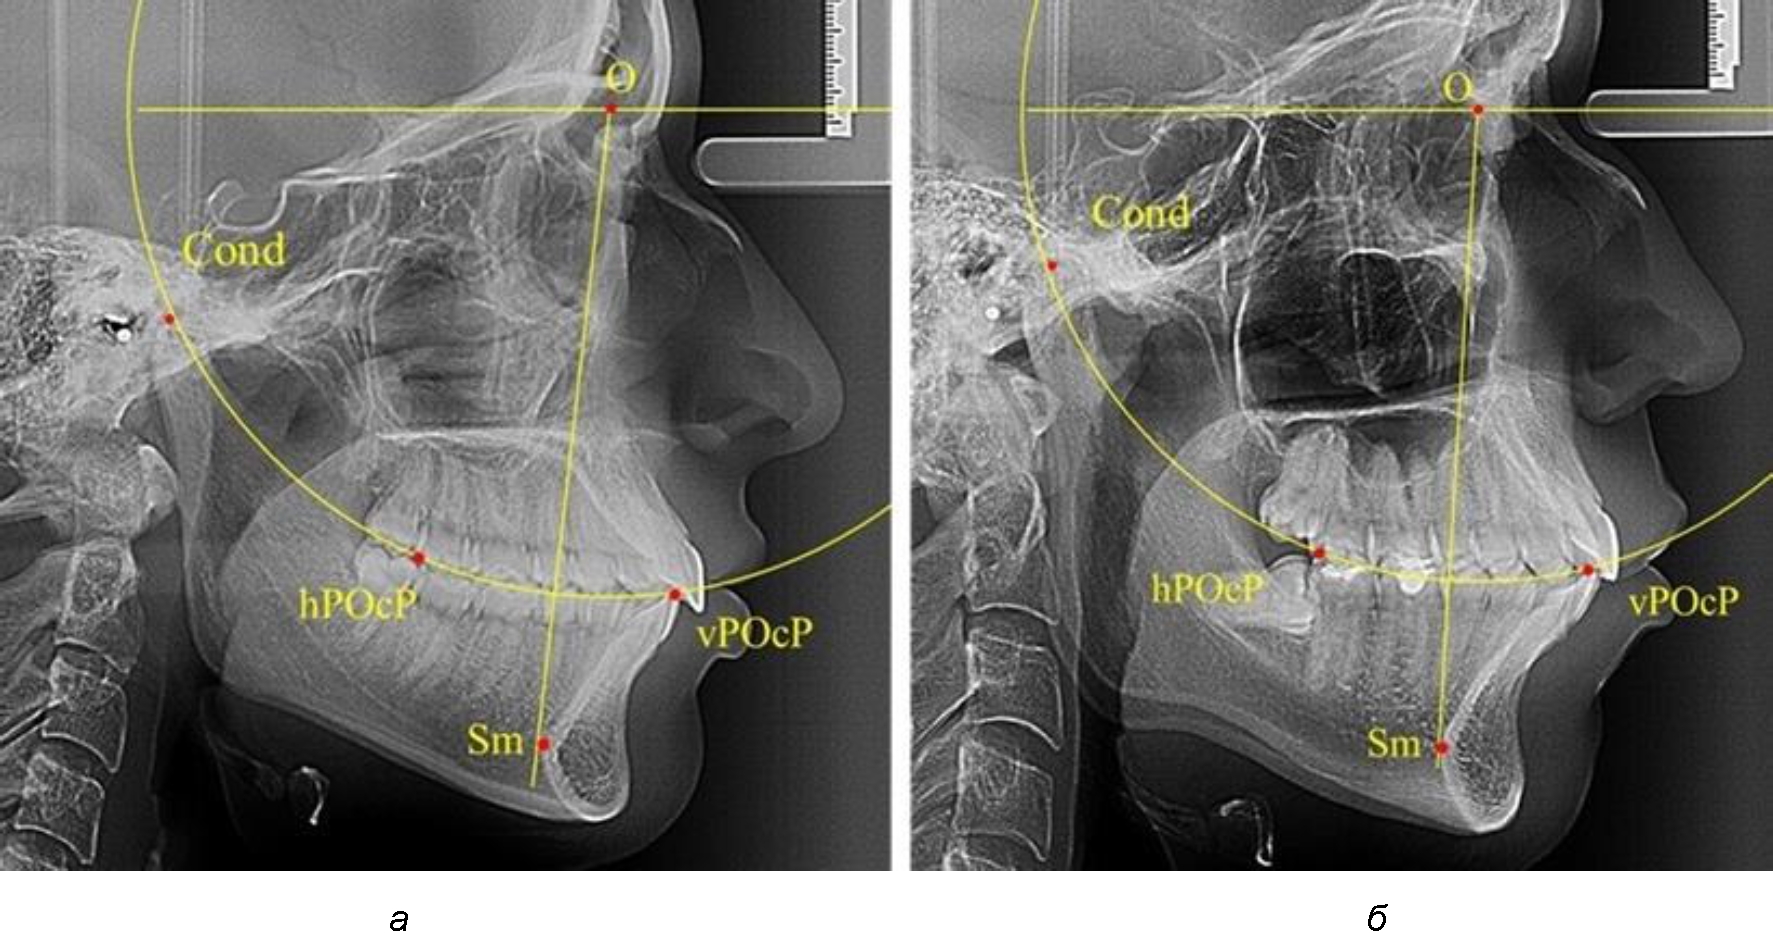

Анализ снимков проводили с использованием традиционного построения стресс-оси по Bimler. Для удобства построения использовали компьютерную программу PowerPoint. Основными точками для построения круга были передняя (vPOcP) и дистальная (hPOcP) окклюзионные точки, а также верхняя выпуклость суставной головки (Cond).

Вставка из программы в виде овала накладывалась на фотографию рентгенограммы и ручным способом растягивалась так, чтобы получился круг, проходящий через обозначенные реперные точки.

Центр окружности О, соединяющей точку резцового перекрытия с жевательной поверхностью зубов и серединой суставных головок, соединяли с выступающей точкой Sm на внутреннем контуре подбородка (рис. 1).

Рис. 1. Метод анализа ТРГ по Bimler

В норме, по резульатам исследования автора, линия Bimler проходила по вертикальной оси первых премоляров, что мы также расценивали как оптимальное их расположение.

Результаты исследования рентгенограмм с мезотрузионным типом резцов показали, что линия Bimler проходила позади первых премоляров у людей с широким типом подбородочного выступа, однако окклюзия была физиологической и не требовала удаления премоляров, что носило рекомендательный характер при проведении подобных исследований при аномалиях прикуса. У людей со средними формами подбородочного выступа линия Bimler проходила впереди первых премоляров (рис. 2).

Аналогичная ситуация была у людей и с узкими вариантами подбородочного выступа.

Таким образом, при мезотрузионном типе зубочелюстных дуг расположение премоляра впереди линии Bimler при широких вариантах подбородка не может быть критерием выбора экстракционных методов лечения.

Рис. 2. Положение первых верхних премоляров при мезотрузии с широкими (а) и средними (б) размерами подбородка